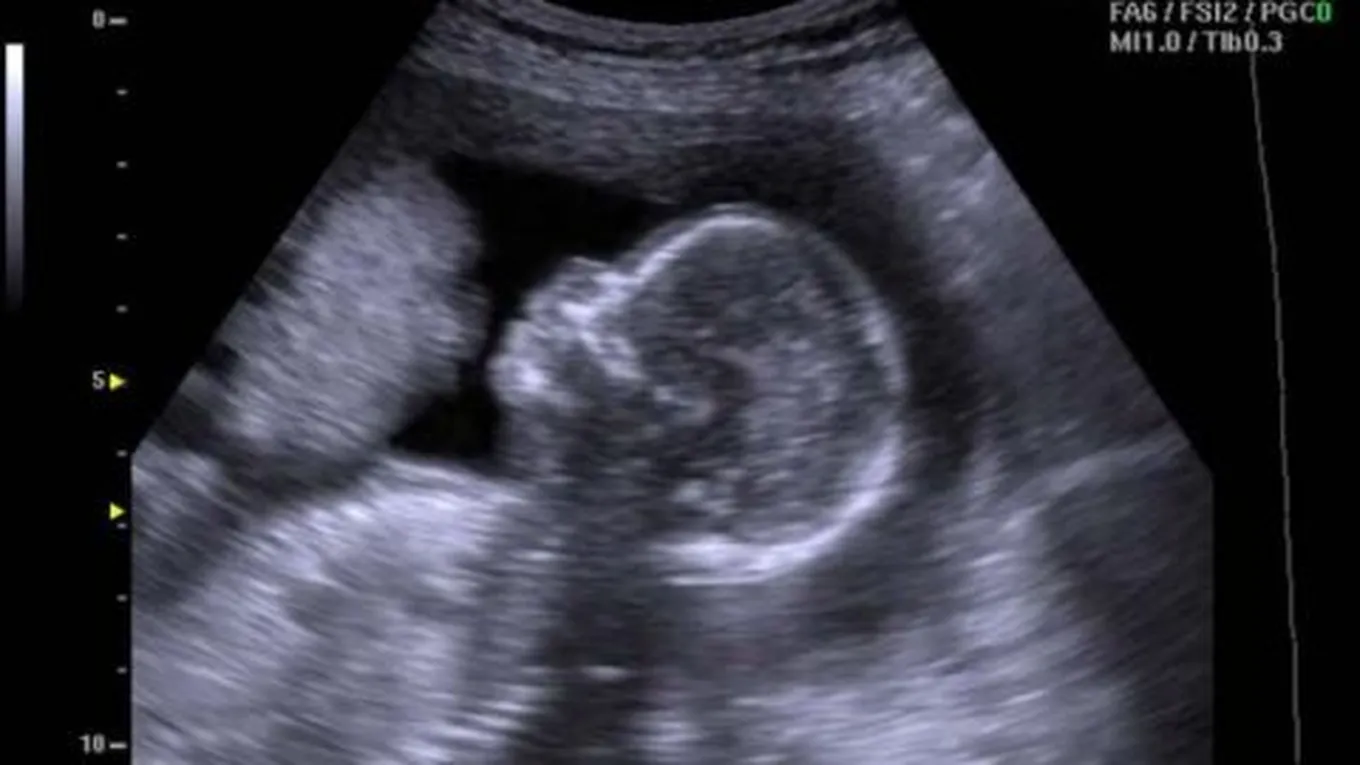

ظهور كيس الجنين في السونار

يظهر كيسُ الحمل في الغالب في الأسبوع الخامس من بداية الحمل، أيّ بعد مرور أسبوع من غياب الدورة الشهريّة، قد يقوم الطبيب بذلك من خلال السونار المهبليّ، حيث إنّ السونار المهبليّ أكثر دقةً في تحديد موقع كيس الجنين، أمّا إذا تعذّر استخدام السونار المهبليّ لأيّ سببٍ كان، فمن الممكن استخدام سونار البطن، إلا أنّ كيس الحمل في الأسبوع الخامس يظهر فارغاً وعادةً لا يشكل ذلك القلق، حيث سيطلبُ الطبيب من المرأة الحامل العودة بعد أسبوعيْن من غياب الدورة الشهريّة، أي في الأسبوع السابع من الحمل؛ للتأكّد من وجود الجنين في كيس الحمل.

أمّا إذا ما استمرّ ظهور كيس الحمل فارغاً، فيجب عندها إعادة فحص مستويات الحمل في الدم؛ للتأكّد من زيادتها كدلالة على الحمل، وعند تأكيد ذلك سيعيدُ الطبيب فحص السونار بعد الأسبوع الثامن، أما إذا لم يظهرْ بعد ذلك فهذا يشيرُ إلى احتماليّة حدوث الحمل خارجَ الرحم، وستكون هناك حاجةٌ إلى البحث عن مكان وجود الحمل، والعمل على إجهاضه إذا كان بقاؤه يهدّد حياةَ الأم.